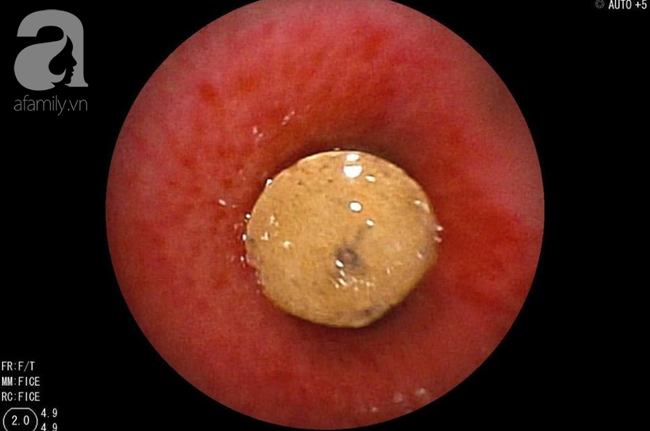

TS.BS Trịnh Hồng Nhiên, Trưởng khoa Hô Hấp BV cho biết sau khi hội chẩn, ông đã chú ý đến vùng bẫy không khí trong phim chụp X-quang phổi. Kết hợp với phim CT scan ngực cho thấy có sự hiện diện của một vật thể lạ trong phế quản, dạng hình trụ, bít lòng hoàn toàn nhánh phế quản S9.

Điều này dẫn tới việc không khí không thể đi qua hoàn toàn vật thể, gây tắc và xẹp toàn bộ nửa phổi phải.

Các BS quyết định phải soi phế quản khẩn cấp. Kết quả là ekip phát hiện một mẩu nhựa cứng khô mà trước đó các BS còn mường tượng là cục đá.

Dị vật được lấy ra hết sức cẩn thận và cũng đầy thử thách vì nằm sâu trong phởi và trơn trượt, lại kẹt bít lòng phế quản đã phù nề, viêm trợt do bị chèn ép.